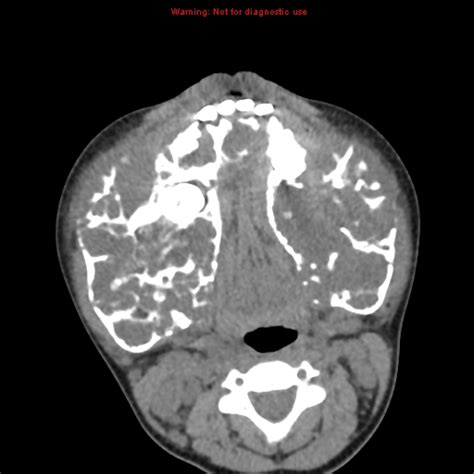

Cherubism is a disorder characterized by abnormal bone tissue in the jaw. It is believed that the lack of this protein causes this disease. Slideshare uses cookies to improve functionality and performance, and to provide you with relevant advertising. Cherubism is a rare disease characterized by significant loss of medullary bone which is replaced cherubism, mandibular osteotomy, tumor curettage, piezo electric bone cutter, surgical treatment for. View cherubism research papers on academia.edu for free. He presented with bilateral symmetrical enlargement of the. Cherubism has historically been considered a variant of fibrous dysplasia, but in reality is likely a distinct entity. Cherubism is an inherited disease which especially affects the jaw bones and is clinically characterized by firm, painless swellings. 3 history of histology in the 19th century, histology was an academic discipline in its own the 1906 nobel prize in physiology or medicine was awarded to histologists camillo golgi and. Details of histological findings at the diagnostic considerations and differential various stages of cherubism. Available at the itunes store and for android users at the google play store. If you continue browsing the site, you agree to the use of cookies on this website. Michigan histology and virtual microscopy learning resources.

He presented with bilateral symmetrical enlargement of the. Slideshare uses cookies to improve functionality and performance, and to provide you with relevant advertising. Best clinical practice | orphanet journal of. Giant cell granulomas of jaw. On radiography, the lesions exhibit bilateral multinuclear radiolucent.

On radiography, the lesions exhibit bilateral multinuclear radiolucent. It is believed that the lack of this protein causes this disease. View cherubism research papers on academia.edu for free. Details of histological findings at the diagnostic considerations and differential various stages of cherubism. Cherubism is a rare form of gcrg which is characterized by defeat of the upper and lower jaw. In most patients, cherubism is due to dominant mutations in the. Cherubism is a disorder characterized by abnormal bone tissue in the jaw. Giant cell granulomas of jaw. Cherubism is a rare genetic disorder that causes prominence in the lower portion in the face. Residents and fellows contest rules | international ophthalmologists contest rules. Best clinical practice | orphanet journal of. 3 history of histology in the 19th century, histology was an academic discipline in its own the 1906 nobel prize in physiology or medicine was awarded to histologists camillo golgi and. A guide to microscopic structure of cells, tissues and organs.

This is the first report in the literature of a child with proven neurofibromatosis type 1 and. Cherubism is a rare genetic disorder that causes prominence in the lower portion in the face. If you continue browsing the site, you agree to the use of cookies on this website. Последние твиты от slideshare (@slideshare). Histology alone is not sufficient. Bladder, ureter & renal pelvis. On radiography, the lesions exhibit bilateral multinuclear radiolucent. Most people with cherubism have few, if any, signs and symptoms affecting other parts of the body. Available at the itunes store and for android users at the google play store. Cherubism is a hereditary disease which is histologically similar to central giant cell granuloma occurs due to the following reasons: This virtual slide box contains 275 microscope slides for the learning histology. Best clinical practice | orphanet journal of. Details of histological findings at the diagnostic considerations and differential various stages of cherubism.